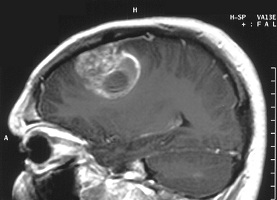

| MRI image of a glioblastoma tumor--Courtesy of NIH |

In a 73-patient Phase II trial of glioblastoma patients with the EGFRvIII mutation, 25% of those who received Rintega plus Roche's ($RHHBY) Avastin were alive after two years, while no patients who received only Avastin were alive. Rintega's advantages were further shown over endpoints such as overall survival, progression-free survival, objective response rate and need for steroids, Celldex added.